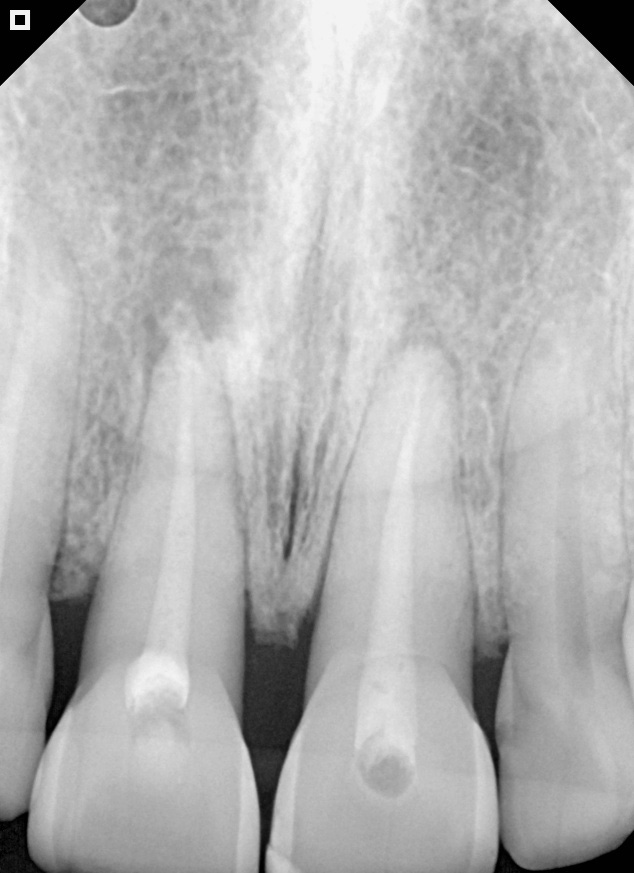

30-day follow-up radiography.